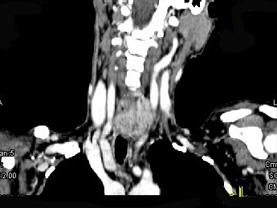

问题 女,50岁,左下颈部扪及一质硬、表面高低不平的包块,约半年,肿块逐渐增大,现感吞咽困难。如图所示CT诊断为()

选项 A.甲状腺癌 B.食管癌 C.喉癌 D.甲状腺原发淋巴瘤 E.颈部神经鞘瘤

答案 A